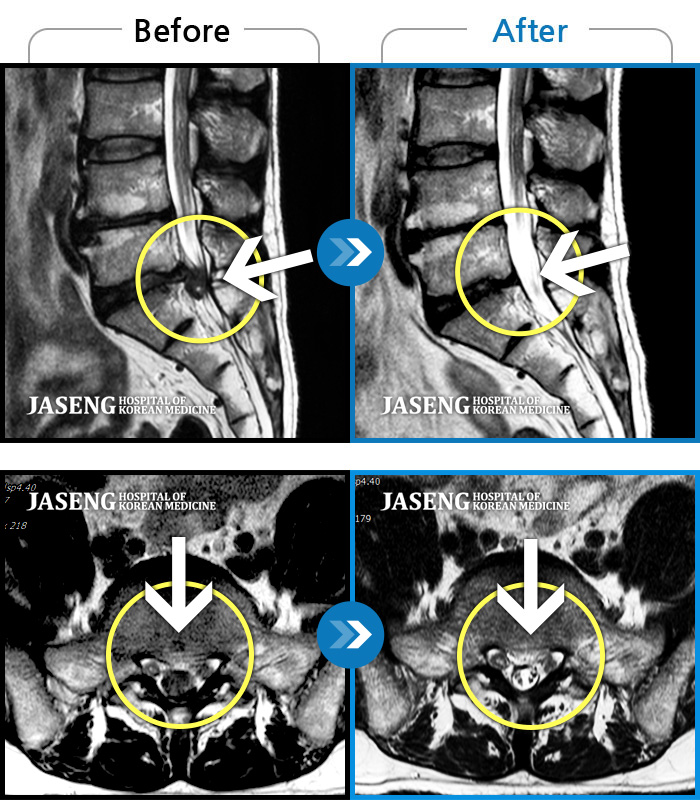

허리디스크

도움받은 사례

강남 · 강만호 원장

허리통증이 심해서 숙이기 어렵고 차에서 내리기 힘들었습니다.

촬영시기

2021.01.06 ~ 2025.03.10

2025.03.20